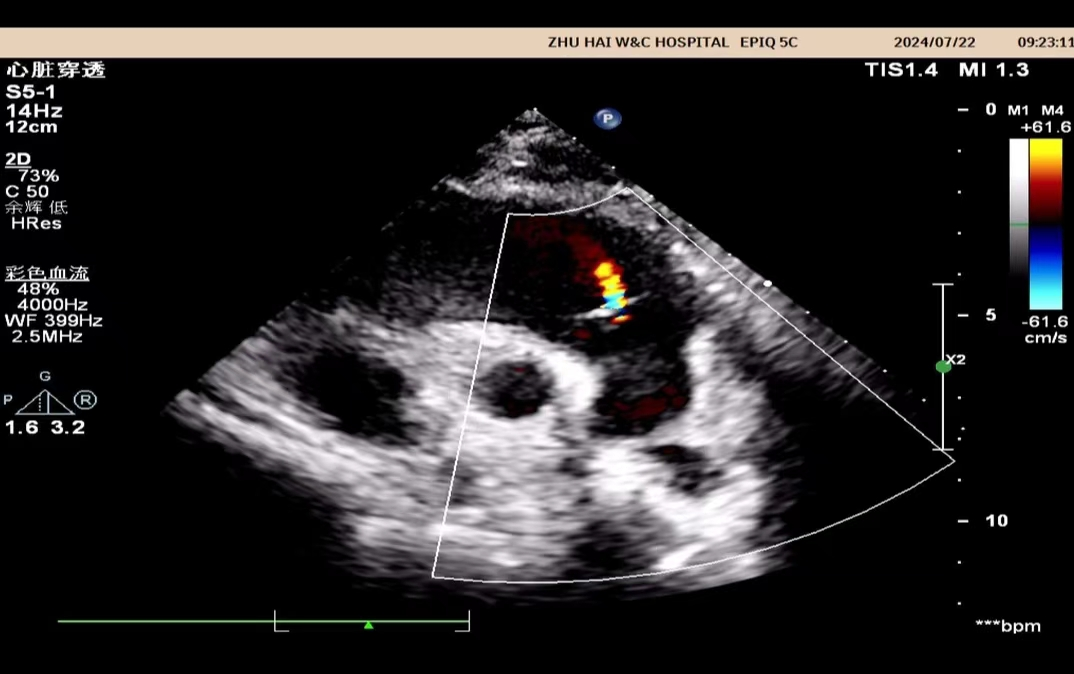

心脏彩超是能够动态显示心腔内部结构、心脏搏动和血液流动情况的一种无创性检查技术。通俗地说,心脏探头有点类似于摄像机的镜头,通过镜头的不断移动和变换,让心脏的各个结构得到准确的呈现,从而让医生能够根据这些图像判断心脏是否存在问题。

它能够比较准确地了解心脏的结构、大小、瓣膜、室壁运动等情况。

比如心包积液,可以评估心包积液的多少,了解有没有心包钙化、心包增厚等。对于心脏临近结构如主动脉、肺动脉可以直观显示,了解这些大血管有没有病变。